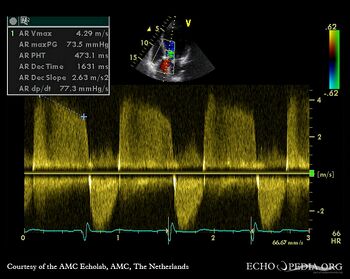

E00343.jpg

Continuous-wave signal of transaortic flow, mild aortic valve stenosis Continuous-wave signal of aortic regurgitation